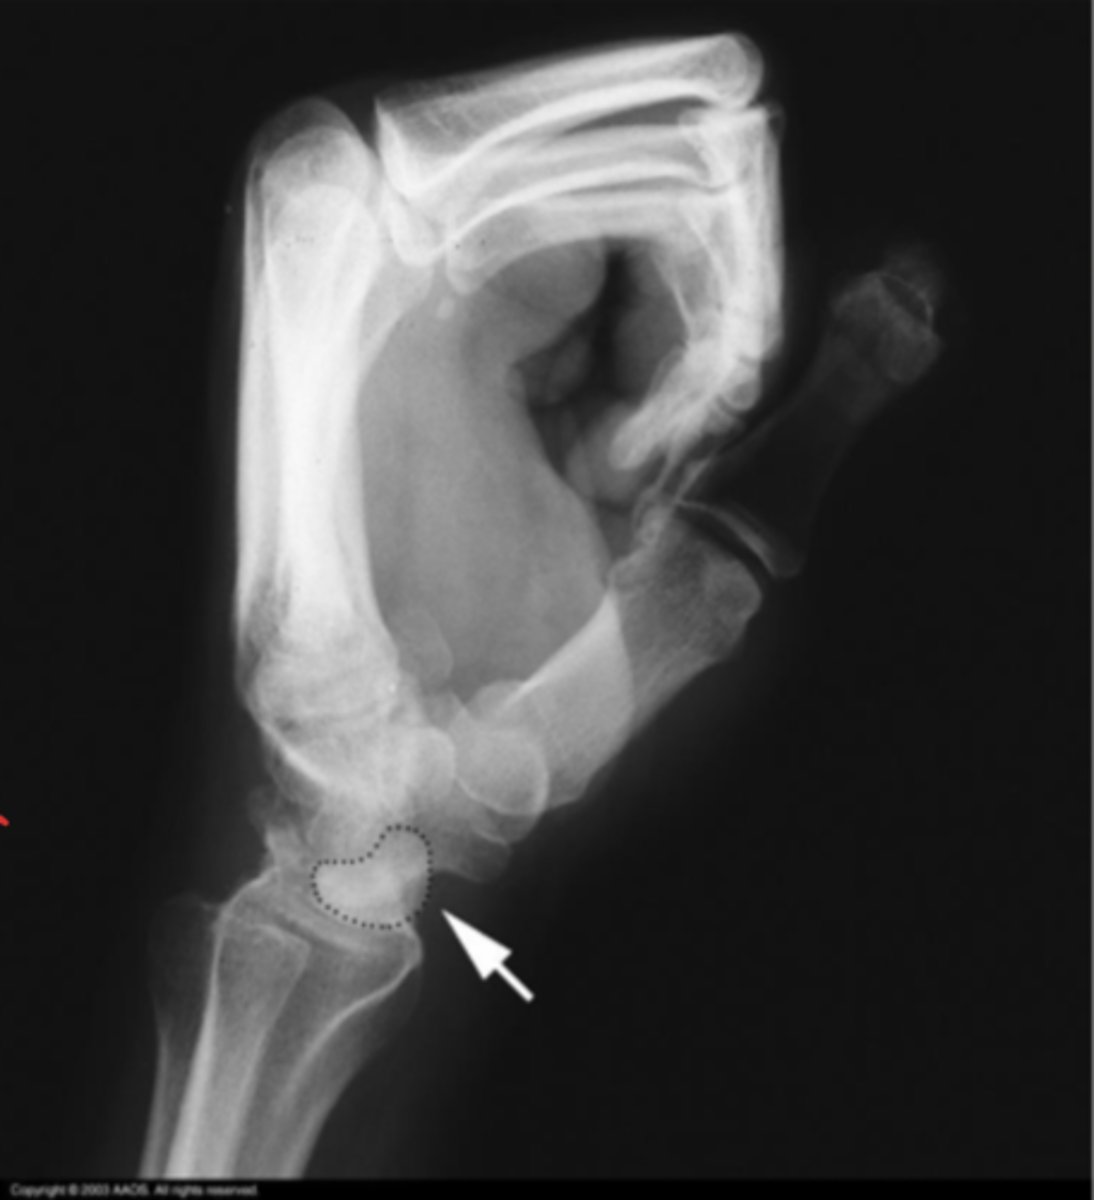

Perilunate instability

What is the issue?